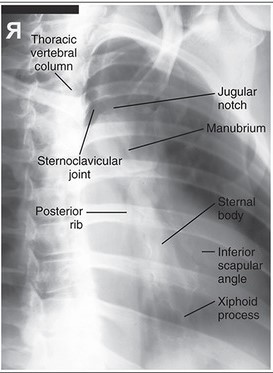

What needs to be demonstrated on an RAO sternum image (film eval)?

slight oblique of sternum utilizing heart shadow

any fractures or inflammatory processes

collimation side to side

marker (L because the right side of the body is not even on the image)

oriented as if person is standing in front of you

What needs to be demonstrated on a lateral sternum image (film eval)?

lateral view of entire sternum

any fractures or inflammatory processes

marker placed anterior for side down (usually L)

collimation anterior to posterior

oriented how you took the image